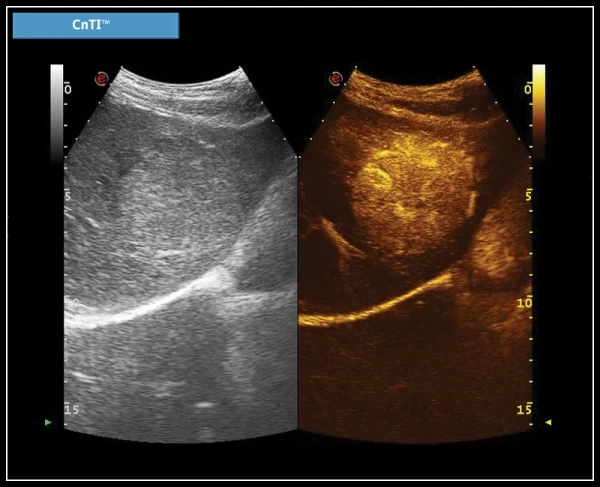

Q-Pack: Q-Pack – это новый мультимодальный инструмент для количественного анализа кривых Контрастной Перфузии (Wi/Wo), с применением Цветного, Энергетического Допплера и технологии CnTI™.

CnTI™ (Технология визуализации контрастов): Высокая чувствительность, глубокое проникновение и высокое разрешение являются основными характеристиками технологии визуализации с усиленным контрастом CnTI™, служащей для улучшения диагностических возможностей.